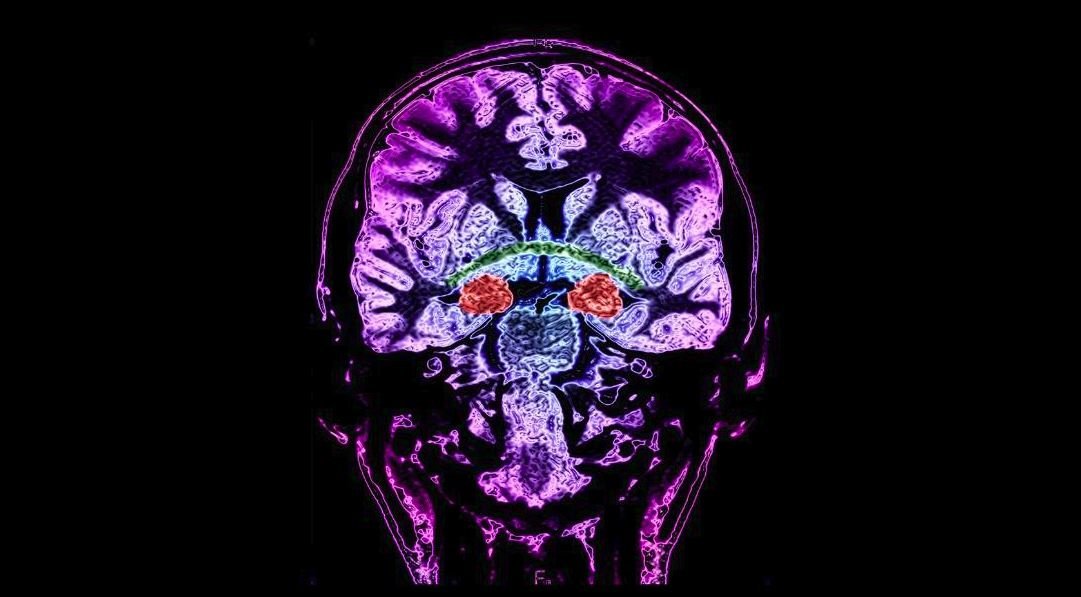

For the study, the researchers searched for progenitor cells and young neurons in 59 postmortem and postoperative human tissue samples taken from the hippocampus. The hippocampus, a tiny seahorse-shaped structure deep inside the brain, plays a major role in learning and remembering. Alvarez-Buylla's research focuses on one brain region at a time.

In fetal samples that had gestated 14 weeks, the researchers saw rich streams of precursor cells and immature neurons migrating to a still-developing region within the hippocampus known as the dentate gyrus, known to be crucial to memory formation.

Searching additional fetal samples, the researchers discovered that by 22 weeks, the migration of cells had decreased. By age 1, there were far fewer immature neurons than during the fetal stage. Older samples showed even fewer young neurons. Age 13 was the oldest brain tissue sample containing any immature neurons, the researchers found.

"In the rat brain, there is a very dense layer of cells, some of which are actively proliferating, and this is where the progenitors of the new neurons meet. This region is called the granular zone," he said. "That structure was simply not there in humans."